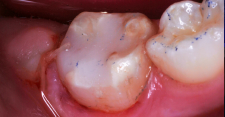

A 9-year-old presented with hypoplasia, hypocalcification, and caries.

Figure 1

A 9-year-old boy had a partially erupted mandibular first molar with much hypocalcification of the occlusal surface and a large caries lesion involving the occlusal and buccal surfaces (Figure 1). The patient complained of continuing sensitivity to cold stimulus and air inspiration. Because the tooth was only partially erupted, consideration for stainless steel crown full coverage had to be delayed. As an interim repair, it was decided to debride the carious tooth substance and place a light-hardened calcium silicate/mineral trioxide aggregate (MTA) liner, followed by a bonded restoration. After inferior alveolar block anesthetic injection and cotton roll isolation, cavity outline form was cut using a high-speed, water-cooled, medium-grit cylindrical diamond bur (Figure 2). Insufficient eruption precluded use of a rubber dam. A large, round bur at slow speed was used to debride the carious enamel and dentin. The prepared surfaces were swabbed for two 60-second applications of a 5% glutaraldehyde/HEMA solution for desensitization and disinfection of the preparation.6,7 Cavity liner was then injected and spread over the deepest sections of the cavity floor and hardened with the visible light beam (Figure 3). After a self-etching bonding agent was applied over the remaining enamel surfaces, without the need for any type of matrix, an RMGI bioactive ionic resin-based composite was injected, in one portion, into the preparation and spread over the four cusps using a ball burnisher. This restorative complex was then photo-polymerized using two 20-second exposures of the visible light beam (1,200 mW/cm2). The restoration was trimmed and finished with large, round diamond burs at slow speed, and occlusion was evaluated with articulating paper and adjusted.